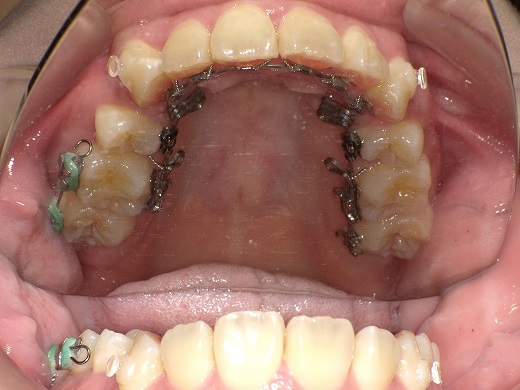

治療前上顎

治療中上顎

治療後上顎